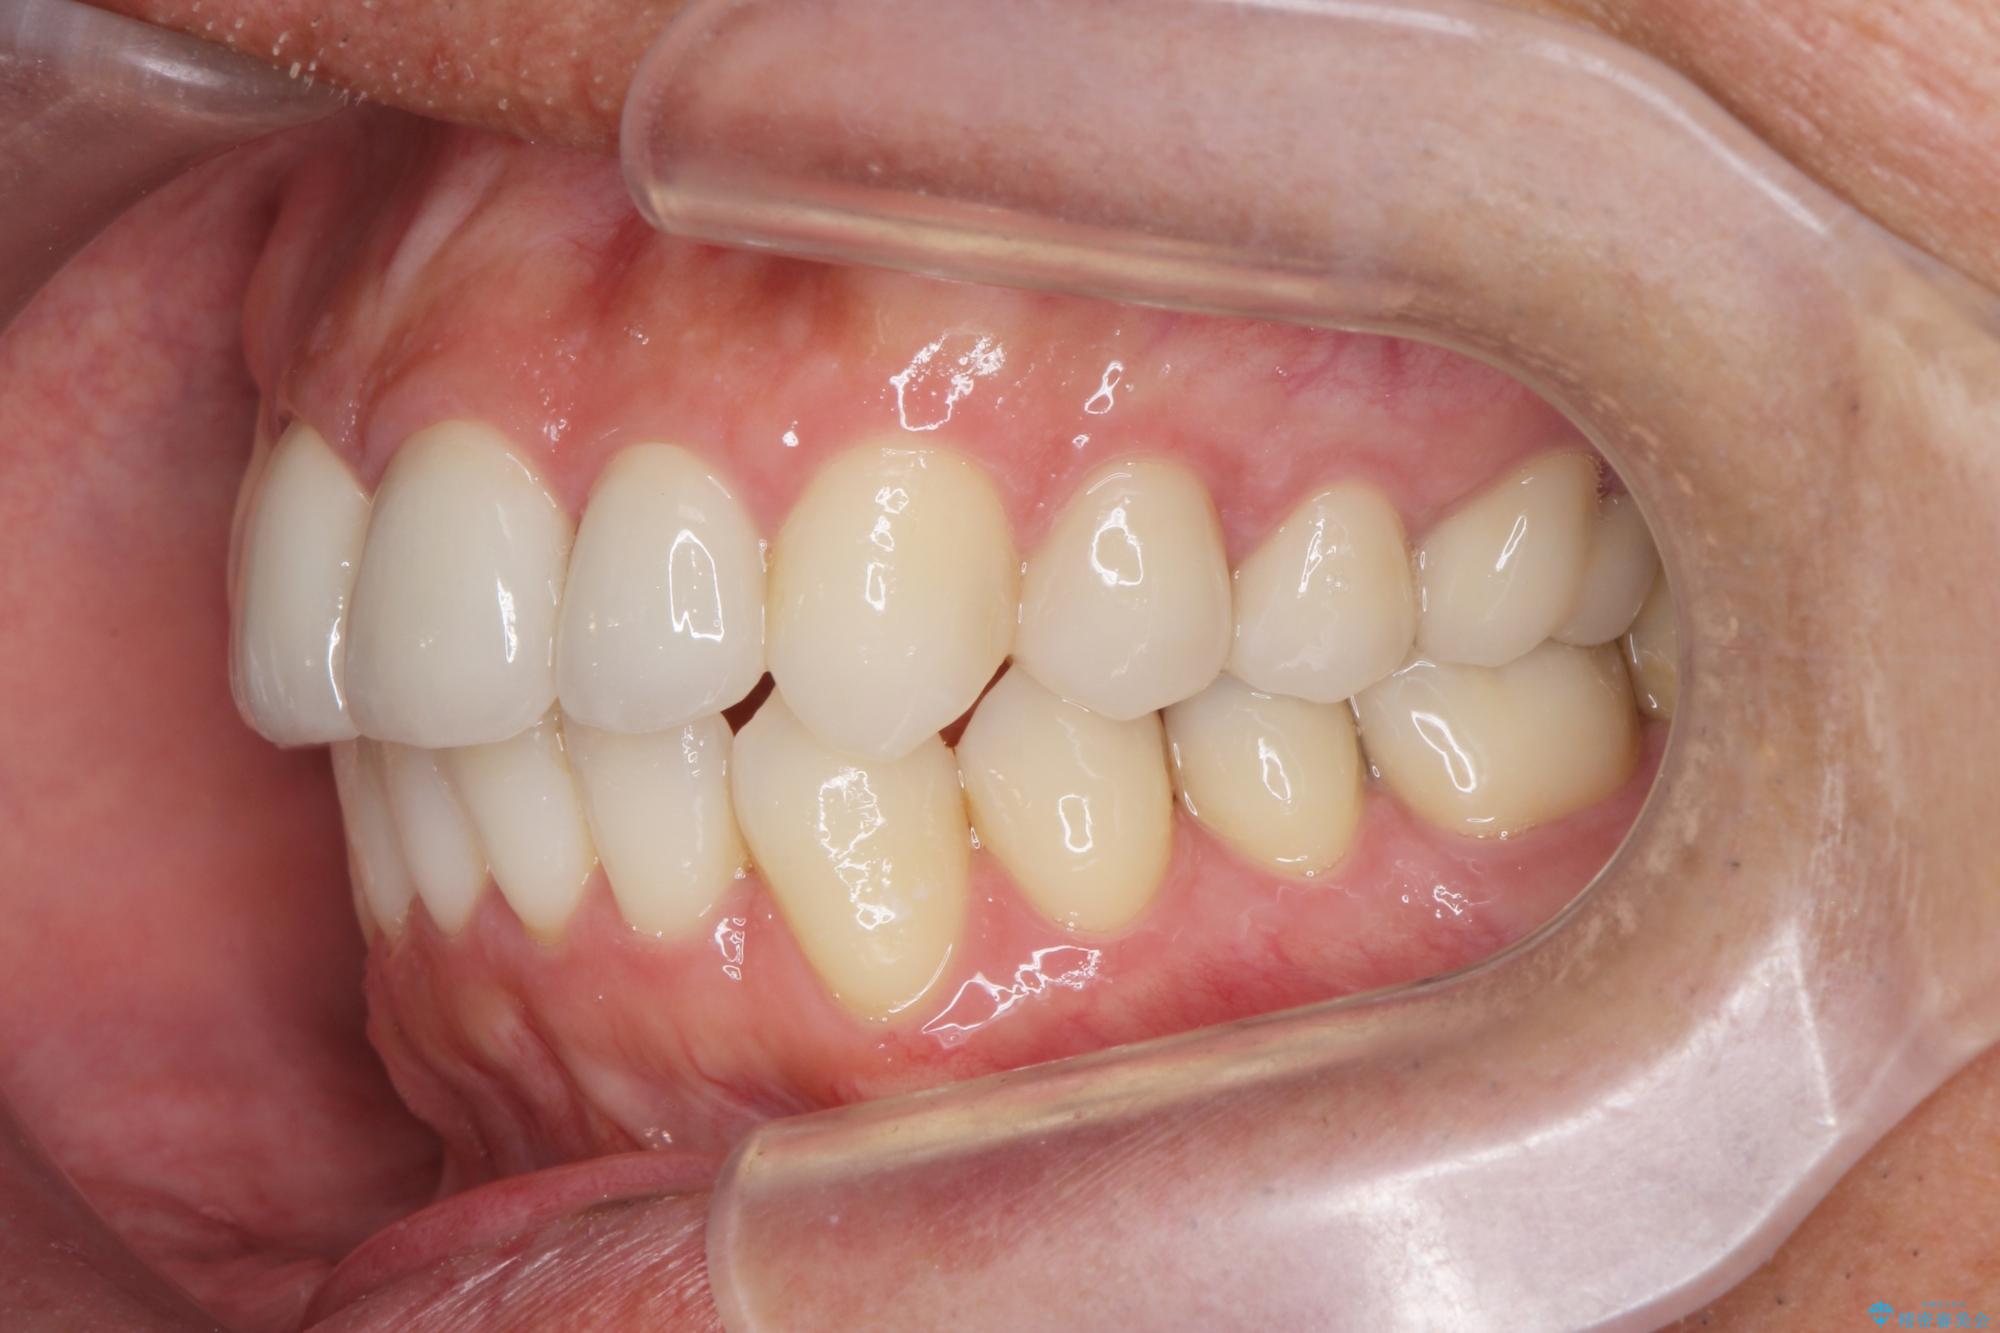

矯正と虫歯のセラミック治療 総合歯科治療の実践

- 突き出た前歯の角度の改善と虫歯治療の改善を求めて来院されました。

虫歯を除去したのち、マウスピース矯正治療を行い、歯並びやがたつきを改善したのち、セラミックに置き換えることで審美性の向上を計画します。